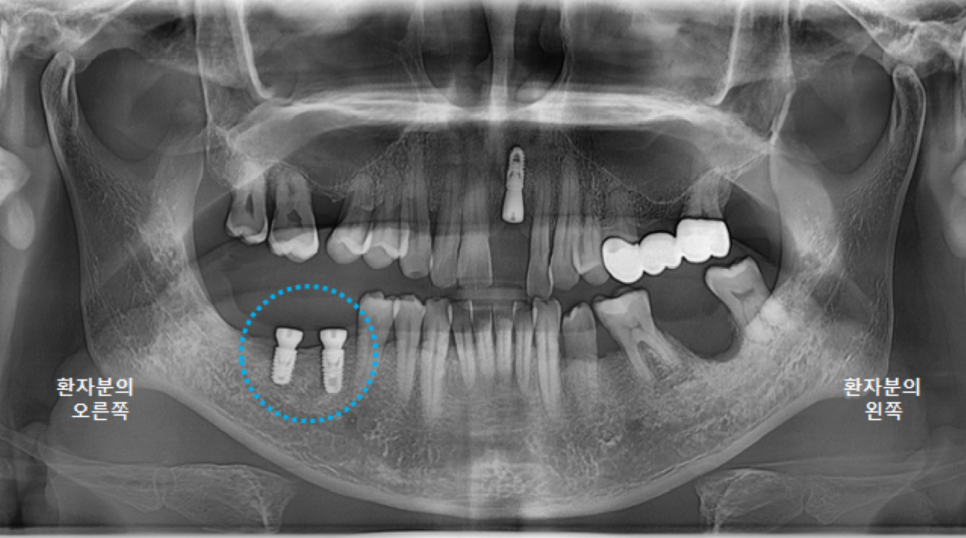

전체적인 구강 판단을 위해

파노라마 엑스레이 사진을 찍었습니다.

왼쪽 큰앞니도 빠져있지만,

오른쪽위 큰어금니, 오른쪽 아래 큰어금니도 발치된 상태였고,

왼쪽 위 브릿지 상태도 좋지는 않았습니다.

왼쪽 아래 큰어금니 하나는 뿌리만 남은 상태였어요.

앞니 임플란트 수술 직후 파노라마 엑스레이 사진입니다.

양옆의 치아 관계도 좋고 뼈이식도 잘 되었습니다. ^^